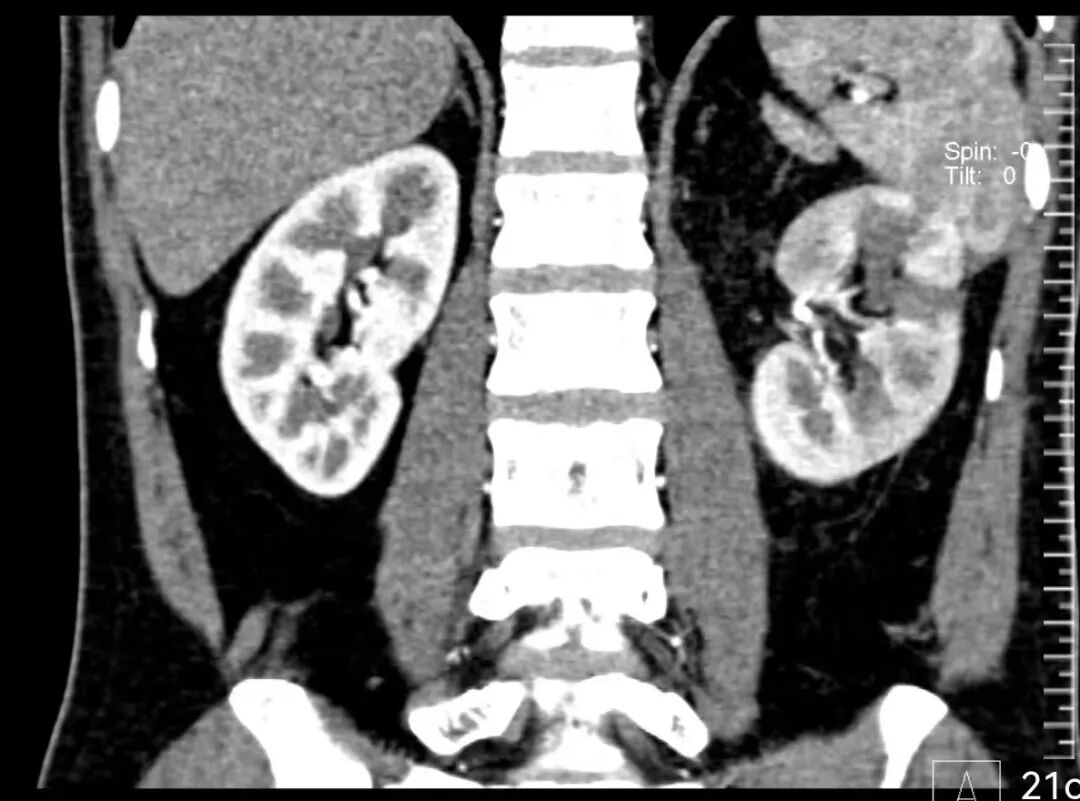

患者文先生在一次常规体检中,意外发现左肾存在一个巨大占位。进一步的增强CT检查结果令人倒吸一口凉气:一个大小约93×82×90mm的类圆形肿瘤从肾脏突出,位置极其凶险,紧贴着肾门部的大血管和集合系统。经专业评估,该肿瘤R.E.N.A.L评分高达11分,属于“高度复杂”级别。